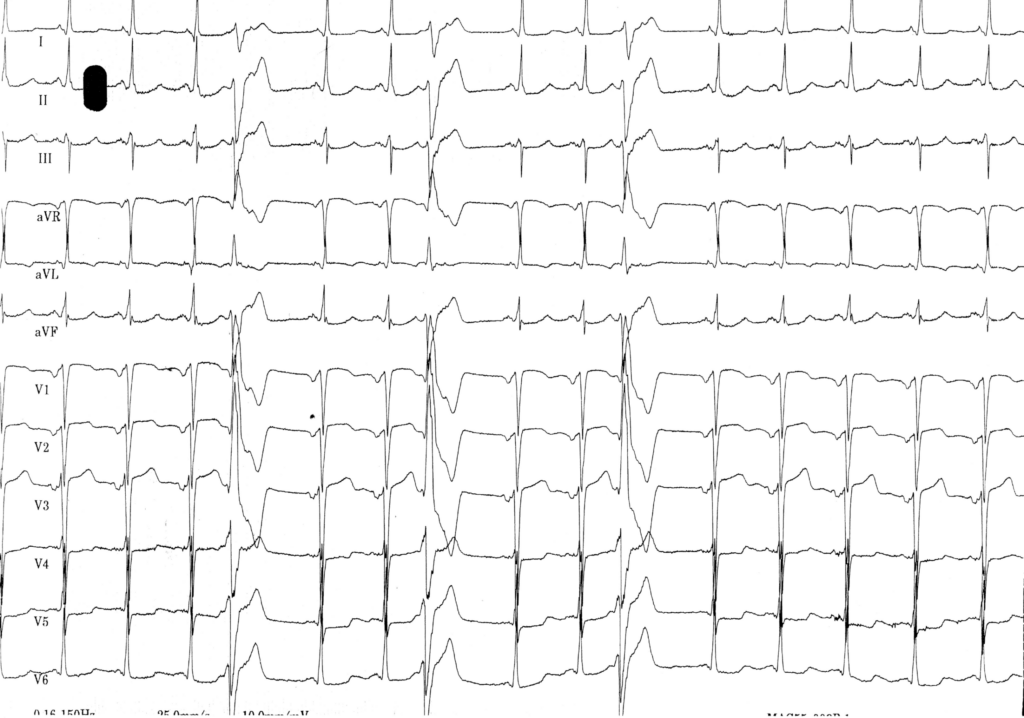

Sur l’électrocardiogramme, une extrasystole ventriculaire se caractérise par l’existence d’un QRS prématuré, ectopique, à QRS large (> 120 ms), sans association avec une activité atriale précédente. Les extrasystoles ventriculaires doivent plus être considérées comme un marqueur de risque qui doit orienter vers la recherche d’une cardiopathie et non comme un facteur de risque indépendant sur lequel il faut agir. La recherche d’une cardiopathie causale est donc un temps essentiel de la prise en charge.

Chez ce patient: 1) l’analyse du QRS conduit sur activité sinusale est très en faveur de l’existence d’une cardiopathie ischémique. On retrouve en effet, des signes d’hypertrophie auriculaire gauche mais également des signes de séquelle de nécrose antérieure confirmés par l’anamnèse et l’analyse des antécédents du patient. 2) la morphologie des extrasystoles est également en faveur de l’existence d’une cardiopathie. La largeur des complexes QRS ectopiques est importante et dépasse les 180 ms ce qui est évocateur d’une cardiopathie, les extrasystoles bénignes survenant sur coeur sain étant généralement plus fines (de l’ordre de 140 ms). Les extrasystoles ont un aspect crocheté, polyphasique et une amplitude relativement faible, autant d’arguments en défaveur d’un caractère bénin. La fragmentation des extrasystoles est considéré comme un facteur péjoratif car traduisant une propagation de l’influx électrique à travers un myocarde ventriculaire aux propriétés de conduction altérées, dans un myocarde cicatriciel ou fibrosé. Chez les patients avec myocardiopathie ischémique, le retard et l’axe des extrasystoles sont souvent dictés par la localisation de la séquelle de nécrose puisque ces extrasystoles sont soit le reflet d’une activité normale de cellules au fonctionnement altéré par l’ischémie, soit le résultat d’une réentrée autour de circuits à propagation lente de l’influx électrique dans les zones cicatricielles.